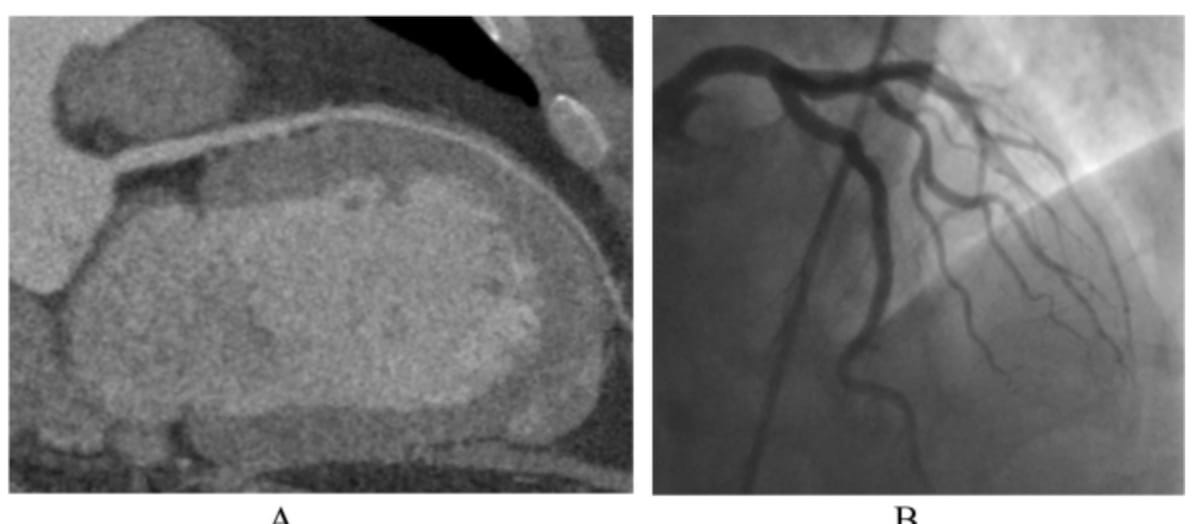

Here one can see examples of coronary CT angiography (CCTA) (left) and invasive coronary angiography (ICA) (right) with both revealing no pathological findings. (Images courtesy of European Radiology.)

Emerging research shows significant patient preference for coronary computed tomography angiography (CCTA) over invasive coronary angiography (ICA).

For the randomized study, recently published in European Radiology, researchers examined findings from 24-hour post-op and long-term follow-up patient questionnaires (median of 3.7 years) for 329 patients who underwent CCTA (167 patients) or ICA (162 patients) for suspected coronary artery disease (CAD).